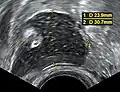

Dermoid cyst in vaginal ultrasonography

A complex cyst due to a dermoid as seen on ultrasound